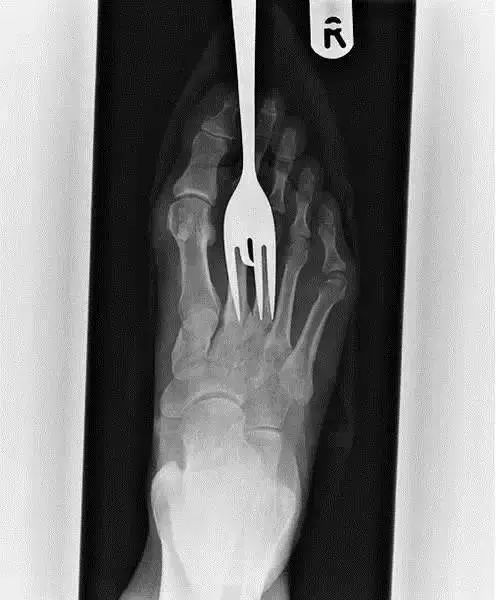

16、这张X光片显示,这位可怜的病人的右脚被叉子扎伤了。